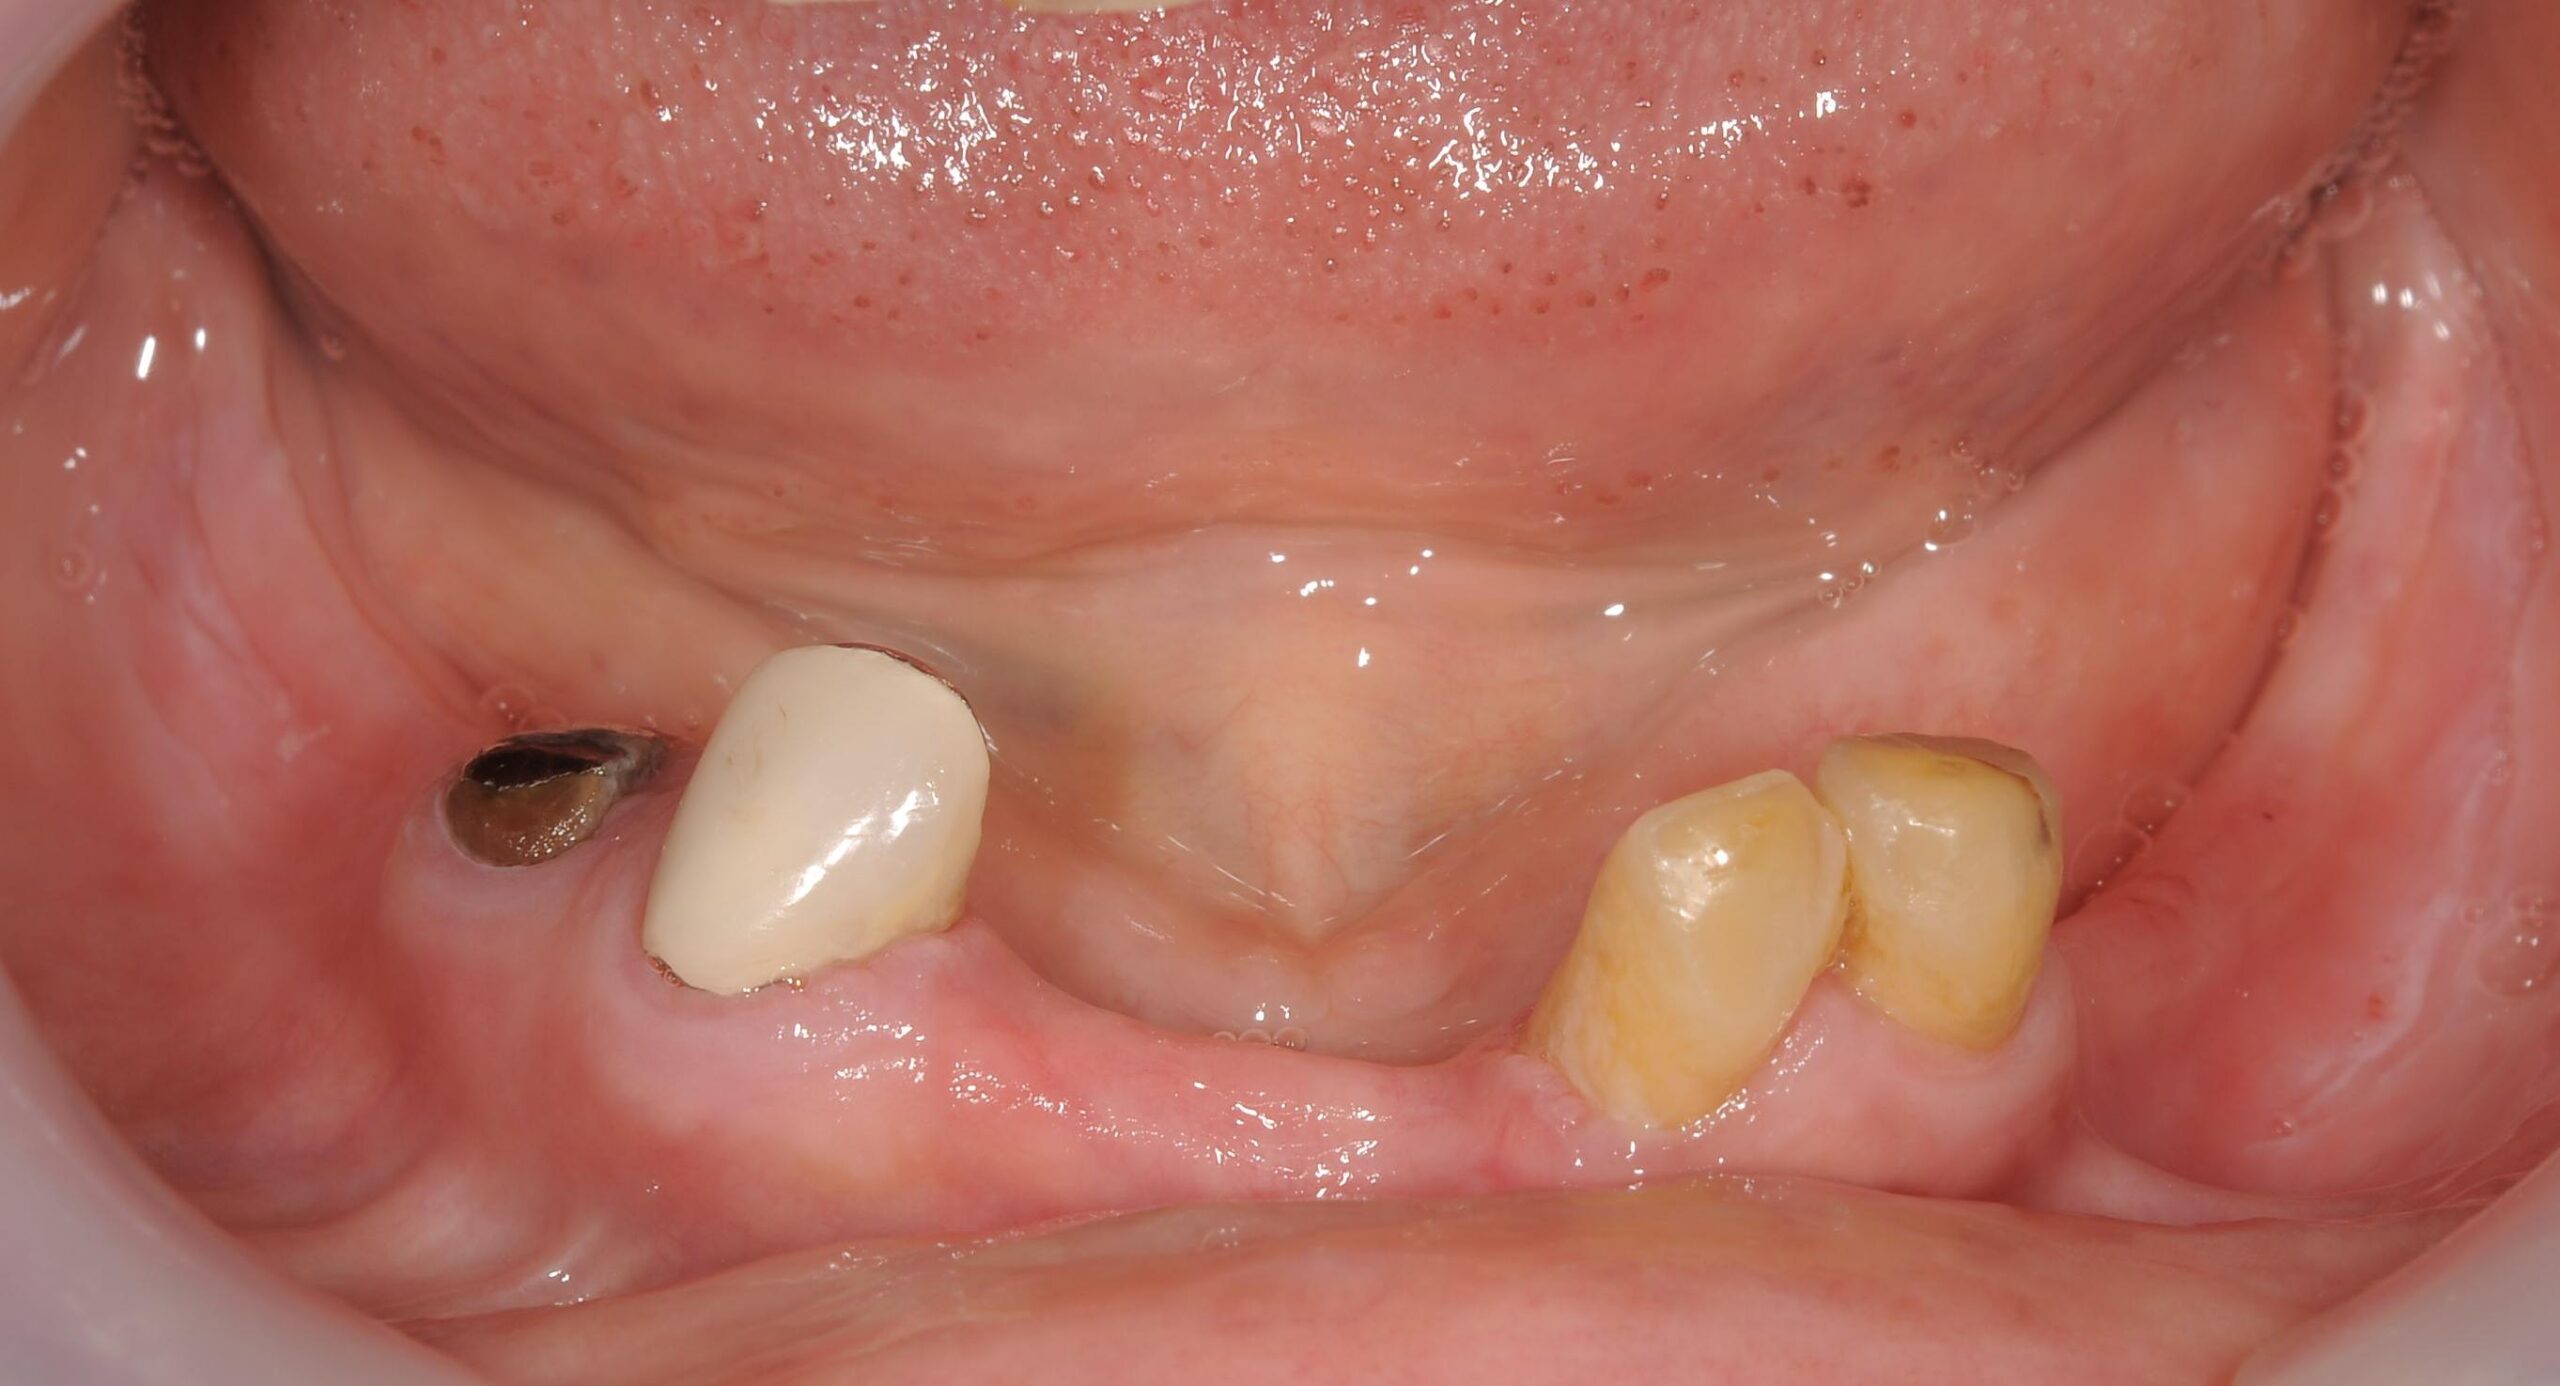

術前のパノラマレントゲン、下顎の骨は十分な高さが無いので下顎管を避けて傾斜埋入が必要でした。

歯の数が少なく、十分に咀嚼することが難しい状態です。